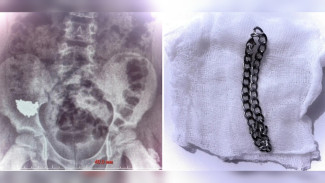

В Воронеже школьник проглотил 20-сантиметровую цепочку

Малышу пришлось делать операцию.